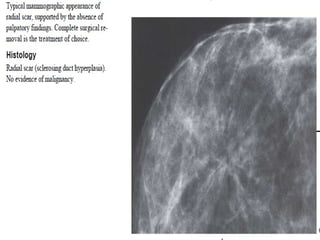

The term architectural distortion is used, when the normal architecture is distorted

with no definite mass visible.

This includes thin straight lines or spiculations radiating from a point, and focal

retraction, distortion or straightening at the edges of the parenchyma.

The differential diagnosis is scar tissue or carcinoma.

Architectural distortion can also be seen as an associated feature.

For instance if there is a mass that causes architectural distortion, the likelihood of

malignancy is greater than in the case of a mass without distortion.

Notice the distortion of the normal breast architecture on oblique view (yellow circle)

and magnification view.

A resection was performed and only scar tissue was found in the specimen.

Architectural distortion